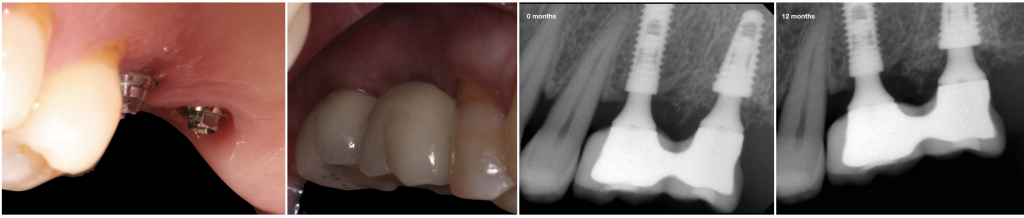

Fig. 4- Follow up after 12 months. Peri-implant soft and hard tissue was well preserved.

During the observation period (12 months), the four implants were osseointegrated, and functional, mechanical or biological complications were not reported. The volume of the soft tissues and the horizontal ridge were lower than in the initial situation. However, the radiographic controls showed bone over the implant platform.

The tapered implant design, with switching platform, had less bone resorption compared with traditional matching implants.16 We used four dental implants (Alvim CM, Neodent) with a tapered design, switching platform, cone morse connection and unpolished surface to get bone over the implant platform leaving the implant placement 2 mm subcrestal. Chu et al. reported that subcrestal placement decreased the peak of compressive stress at the crestal cortical bone and transferred it toward the trabecular bone (Chu 2011).